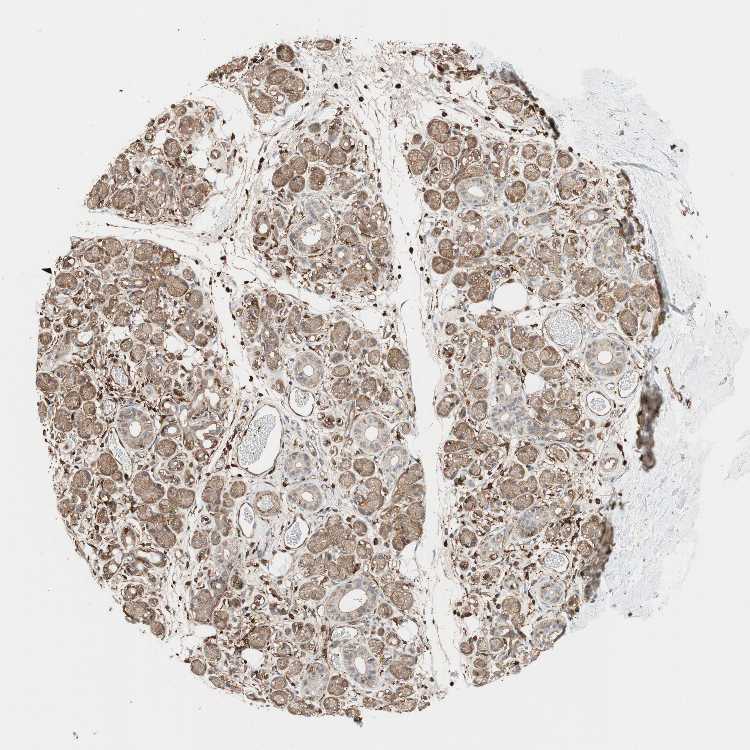

ADIPOSE TISSUE - Antibody stainingi

Antibody staining in the annotated cell types in the current human tissue is reported as not detected, low, medium, or high, based on conventional immunohistochemistry profiling in selected tissues. This score is based on the combination of the staining intensity and fraction of stained cells.

Each image is clickable and will lead to virtual microscopy that enables deeper exploration of all samples and also displays staining intensity scores, fraction scores and subcellular localization as well as patient and tissue information for each sample.

Antibody HPA005724Antibody CAB004612

Adipocytes LowMedium